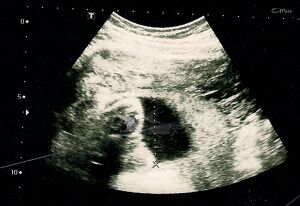

Obstetric ultrasonography is routinely used for dating the gestational age of a pregnancy from the size of the fetus, determine the number of fetuses and placentae, evaluate for an ectopic pregnancy and first trimester bleeding, the most accurate dating being in first trimester before the growth of the foetus has been significantly influenced by other factors.[24] Ultrasound is also used for detecting congenital anomalies (or other foetal anomalies) and determining the biophysical profiles (BPP), which are generally easier to detect in the second trimester when the foetal structures are larger and more developed.[25] Specialised ultrasound equipment can also evaluate the blood flow velocity in the umbilical cord, looking to detect a decrease/absence/reversal or diastolic blood flow in the umbilical artery.[26]

X-rays and computerized tomography (CT) are not used, especially in the first trimester, due to the ionizing radiation, which has teratogenic effects on the foetus.[27] No effects of magnetic resonance imaging (MRI) on the foetus have been demonstrated,[28] but this technique is too expensive for routine observation. Instead, obstetric ultrasonography is the imaging method of choice in the first trimester and throughout the pregnancy, because it emits no radiation, is portable, and allows for realtime imaging.[29]

The safety of frequent ultrasound scanning has not been confirmed. Despite this, increasing numbers of women are choosing to have additional scans for no medical purpose, such as gender scans, 3D and 4D scans.[30] A normal gestation would reveal a gestational sac, yolk sac, and fetal pole.[31]

The gestational age can be assessed by evaluating the mean gestational sac diameter (MGD) before week 6, and the crown-rump length after week 6. Multiple gestation is evaluated by the number of placentae and amniotic sacs present.[32]